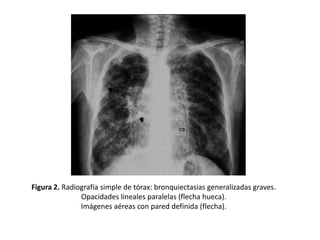

Figura 2. Radiografía simple de tórax: bronquiectasias generalizadas graves.

Opacidades lineales paralelas (flecha hueca).

Imágenes aéreas con pared definida (flecha).

• Opacidades

lineales

paralelas

que

corresponden a bronquios dilatados con la

pared engrosada.

• Dan lugar al signo del “raíl de tranvía” (Figura

2, 3 y 4)